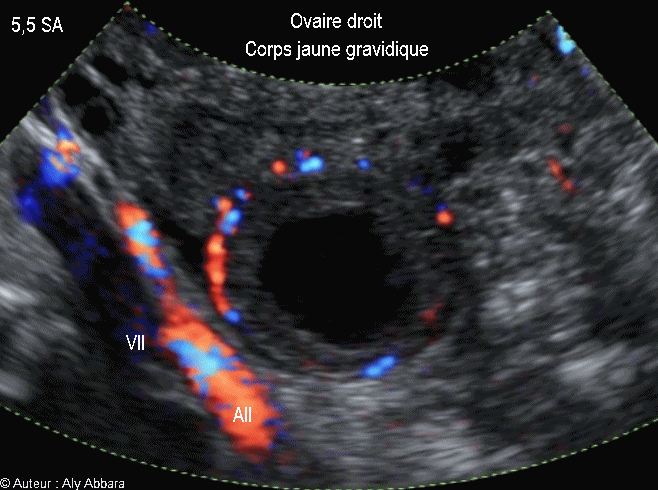

Corps jaune gravidique dans l'ovaire droit - جسم أصفر حملي في المبيض الأيمن -  5,5 SA

Corps jaune gravidique enkysté, de l'ovaire droit - جسم أصفر حملي في المبيض الأيمن -  5,5 SA

• Vidéo et image animée échographiques montrant un corps jaune gravidique, dans l'ovaire, chez une femme enceinte de 5,5 SA :